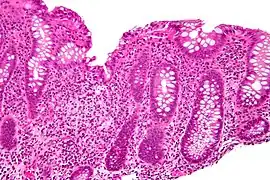

Cryptitis. H&E stain.